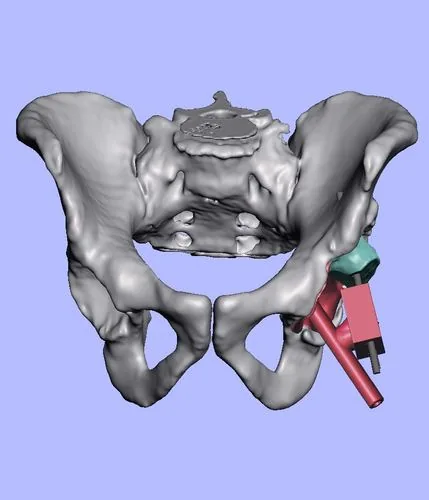

Planificación 3D con biomodelos

Utilizamos tecnología de impresión 3D para crear modelos exactos de tu anatomía antes de la cirugía. Esto nos permite planificar cada detalle con precisión milimétrica y reducir significativamente el tiempo quirúrgico.

Precisión milimétrica

Guías de corte personalizadas basadas en tu anatomía real.

Biomodelos impresos, segmentación digital y planificación 3D aplicada a cirugía de cadera

Preoperatorio

Postoperatorio

Artroplastia bilateral simultánea con utilización de tallo femoral acortado (short stem). Esta opción preserva mayor stock óseo y facilita una fijación biológica óptima. Alta a las 24 horas caminando con andador.